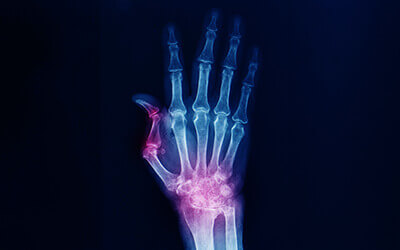

ARTHRITIS OF THE HAND & WRIST

Arthritis is a joint inflammation, with osteoarthritis being the most common type, often affecting the thumb’s base. Symptoms like pain, swelling, and stiffness limit hand movement.

Arthritis Treatment of Thumb

ARTHRITIS OF THE THUMB

Thumb arthritis, a common form of osteoarthritis, affects the joint at the thumb’s base. It’s more frequent in women over 40, causing pain, swelling, stiffness, and reduced thumb mobility.